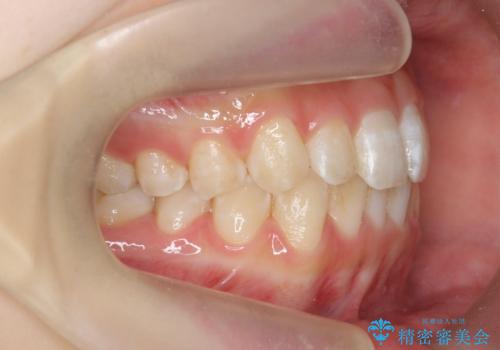

前歯のねじれを治したい マウスピース矯正治療

- 前歯のねじれを改善し、きれいな歯並びにしたい!と矯正治療を希望され来院されました。

マウスピース矯正システム、インビザラインのシミュレーションを用いて最終的な歯の位置をしっかりと確認したのち、きれいな歯並びとなるようマウスピース矯正治療を開始します。

ねじれとともに突き出たように見えていた前歯も見た目が大きく改善し、喜んでいただくことができました。